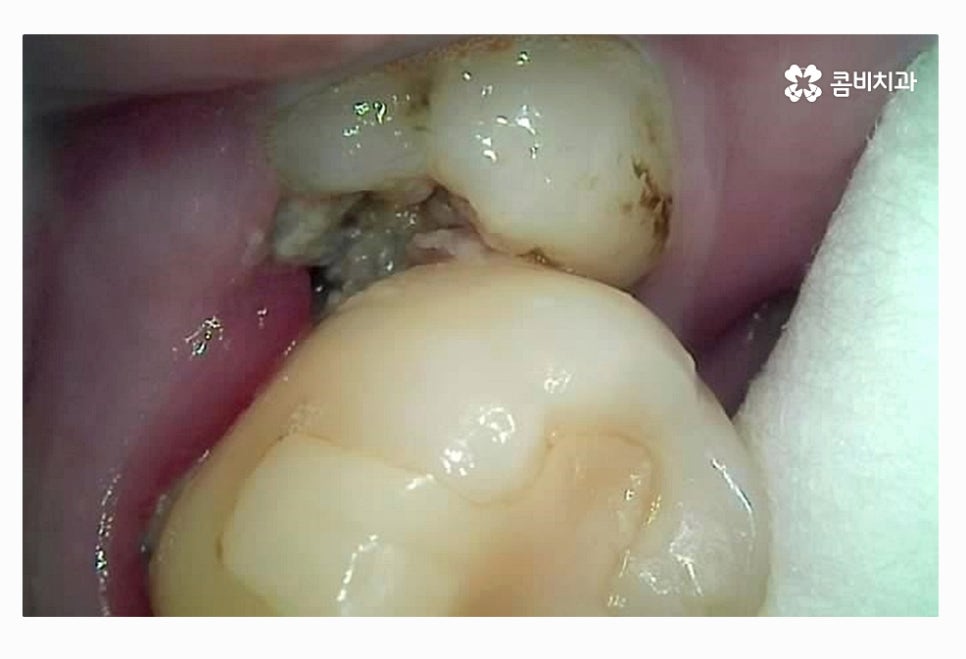

위 환자분처럼 사랑니가 정상적인 위치에서 맹출이 되었다면

청결 관리를 잘한다면 사랑니는 꼭 무조건 발치를

해야 하는 것은 아니지만 사랑니 자체가 치아 중에서도

가장 안쪽에 위치하고 치석 등이 쌓이기 쉽기 때문에

평소 칫솔질을 꼼꼼하게 하더라도 썩기 쉬울 수 있는데요.

이미 사랑니 충치 심해진 상태라면 일반적인 충치 치료를

하는 경우보다는 대부분 발치를 한다고 볼 수 있어요.